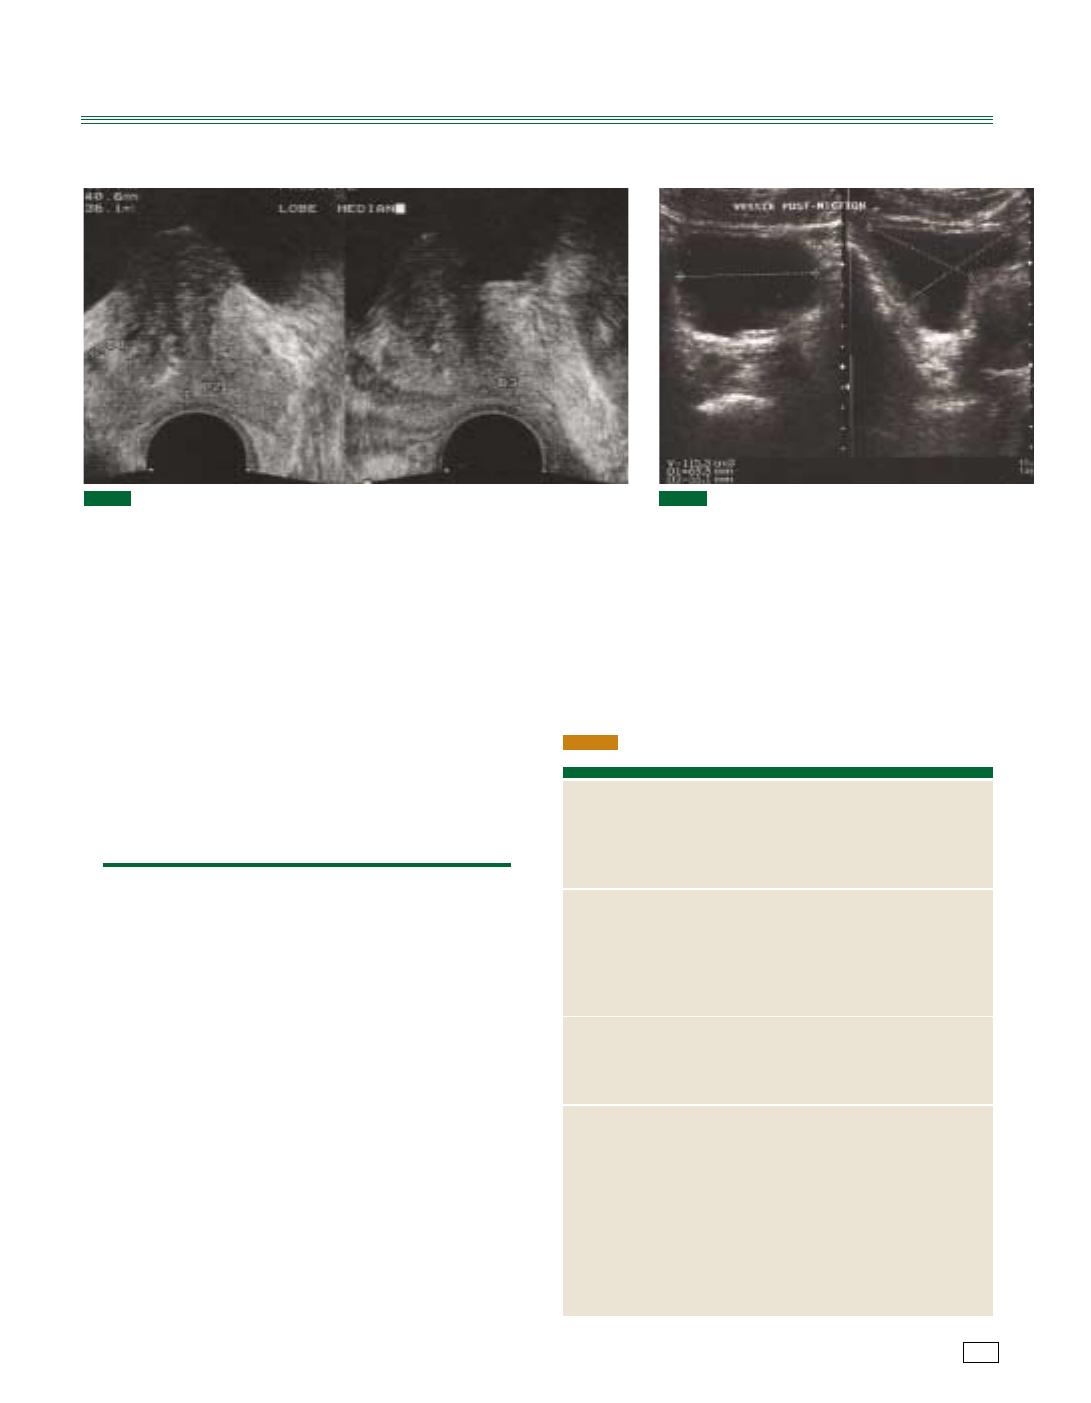

— volume prostatique (fig. 2) ;

— mesure du résidu postmictionnel (pathologique si supérieur à

100 cc) [fig. 3] ;

— recherche d’un résidu postmictionnel (fig. 4) ou d’une urétéro-

hydronéphrose.